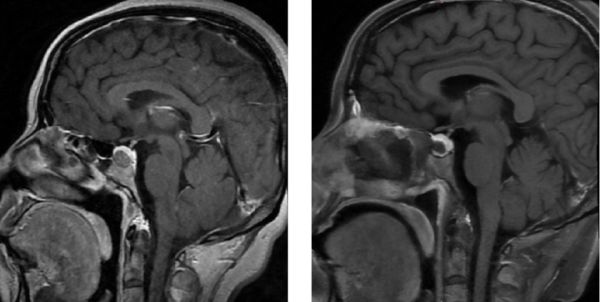

术前和术后磁共振对比,左图为术前,右图为术后

术中,在荧光技术的精准引导下,李奇副主任医师可清晰分辨肿瘤与垂体的分界,使得肿瘤切除过程精准而高效。最终,在完整保留患者垂体功能的前提下,肿瘤被彻底清除。术后影像学检查(MRI)对比显示术前占位的肿瘤影完全消失,周围正常结构完好无损。